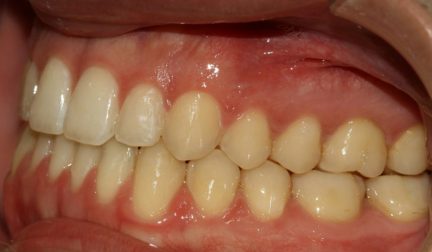

Classe III, béance, arcades étroites, arcades asymétriques, déviation médiane maxillaire, déviation médiane mandibulaire, décalage médian, encombrement, rotations, espacement, diastème

Mésialisation, courbe de Spee nivelée, égression, expansion, rétraction, vestibulo-version, fermeture de l'espace, traitement de phase II, élastiques : Classe III

- Relation de classe I obtenue

- Guidage fonctionnel des canines des deux côtés

- Surplomb et recouvrement normaux obtenus

- Lignes médianes coïncidentes

- Mésialisation de l'arc supérieur (1-2 mm): Classe III molaire et canine à classe I molaire et canine.

- Élastiques de classe III : Molaire et canine de classe III à molaire et canine de classe I. (Temps plein 22 heures/vêtements de jour).